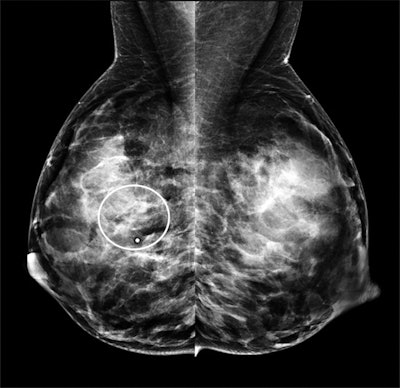

An additional 53 women were recommended for biopsy due to a BI-RADS 4 or 5 lesion on the targeted ultrasound scan. Of these women, five were diagnosed with invasive ductal carcinoma. Mammography identified seven additional suspicious lesions but no additional cancers.

On its own, targeted ultrasound achieved a 100% sensitivity and 67% specificity. When combined with mammography, the modality maintained a 100% sensitivity rate, but the specificity rate dropped to 61%.

The authors attributed mammography's lower specificity due to the modality's struggle depicting cancers in dense breast tissues during pregnancy and lactation. Notably, 98% of the patients in the study had dense breast tissue, including 72% of whom had extremely dense breast tissue.